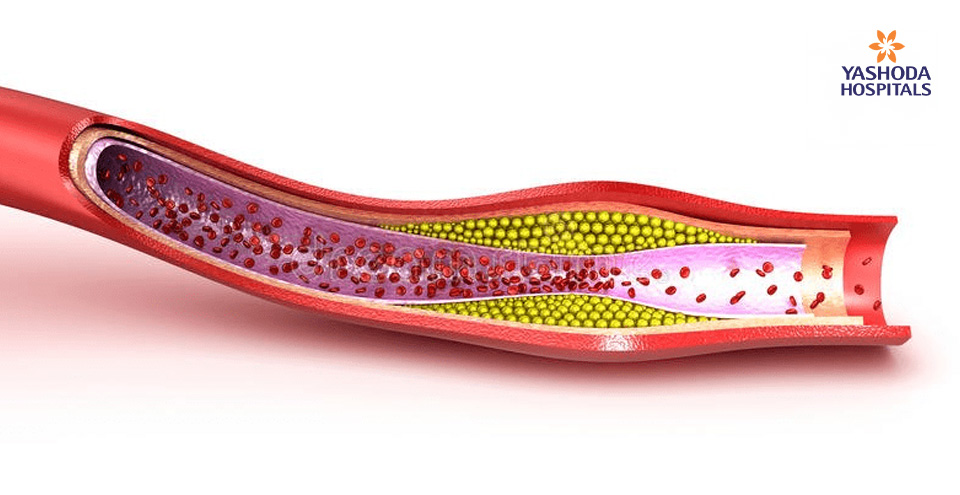

Angioplasty is performed more often as it is a percutaneous procedure and a safer option to remove blockages formed in arteries [Coronary] of the heart. When the patient is above 80 years, the procedure becomes technically difficult because of age-related changes that occur in the body. As the age advances the arteries become harder due to the patho-physiological process of atherosclerosis. This process leads to deposition of calcium in the arterial wall making them harder as compared to the arteries of younger patients. The calcium deposits over the blockage from inside the lumen of the vessel and also on the outer wall of the vessel.

While the blockages in the younger individuals are easy to dilate using the balloon, owing to the softer nature of the block, it is less likely to remove the blockages with similar ease in the elderly. These blocks are relatively difficult to negotiate because of a hard matrix containing calcium and other natural salts in addition to fat. The harder blocks, which cannot be dilated using balloon before deployment of the stent due to calcium deposition, need Rotablation, an interventional tool for debulking the harder lesions.

Rotablator burr: A special catheter, with an acorn-shaped, diamond-coated tip, is guided to the point of narrowing in your coronary artery. The tip spins around at a high speed and grinds away the plaque on your artery walls